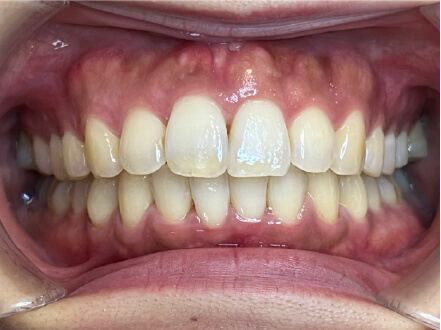

叢生の症例

17歳

女性

相談内容

カウンセリング・診断結果

治療内容・方法

全額アライナー矯正

術後の経過・現在の様子

クリアライナー使用

治療のリスク

痛み・歯根吸収・歯肉退縮・虫歯・後戻り

費用・治療期間

715,000円、2年10ヶ月